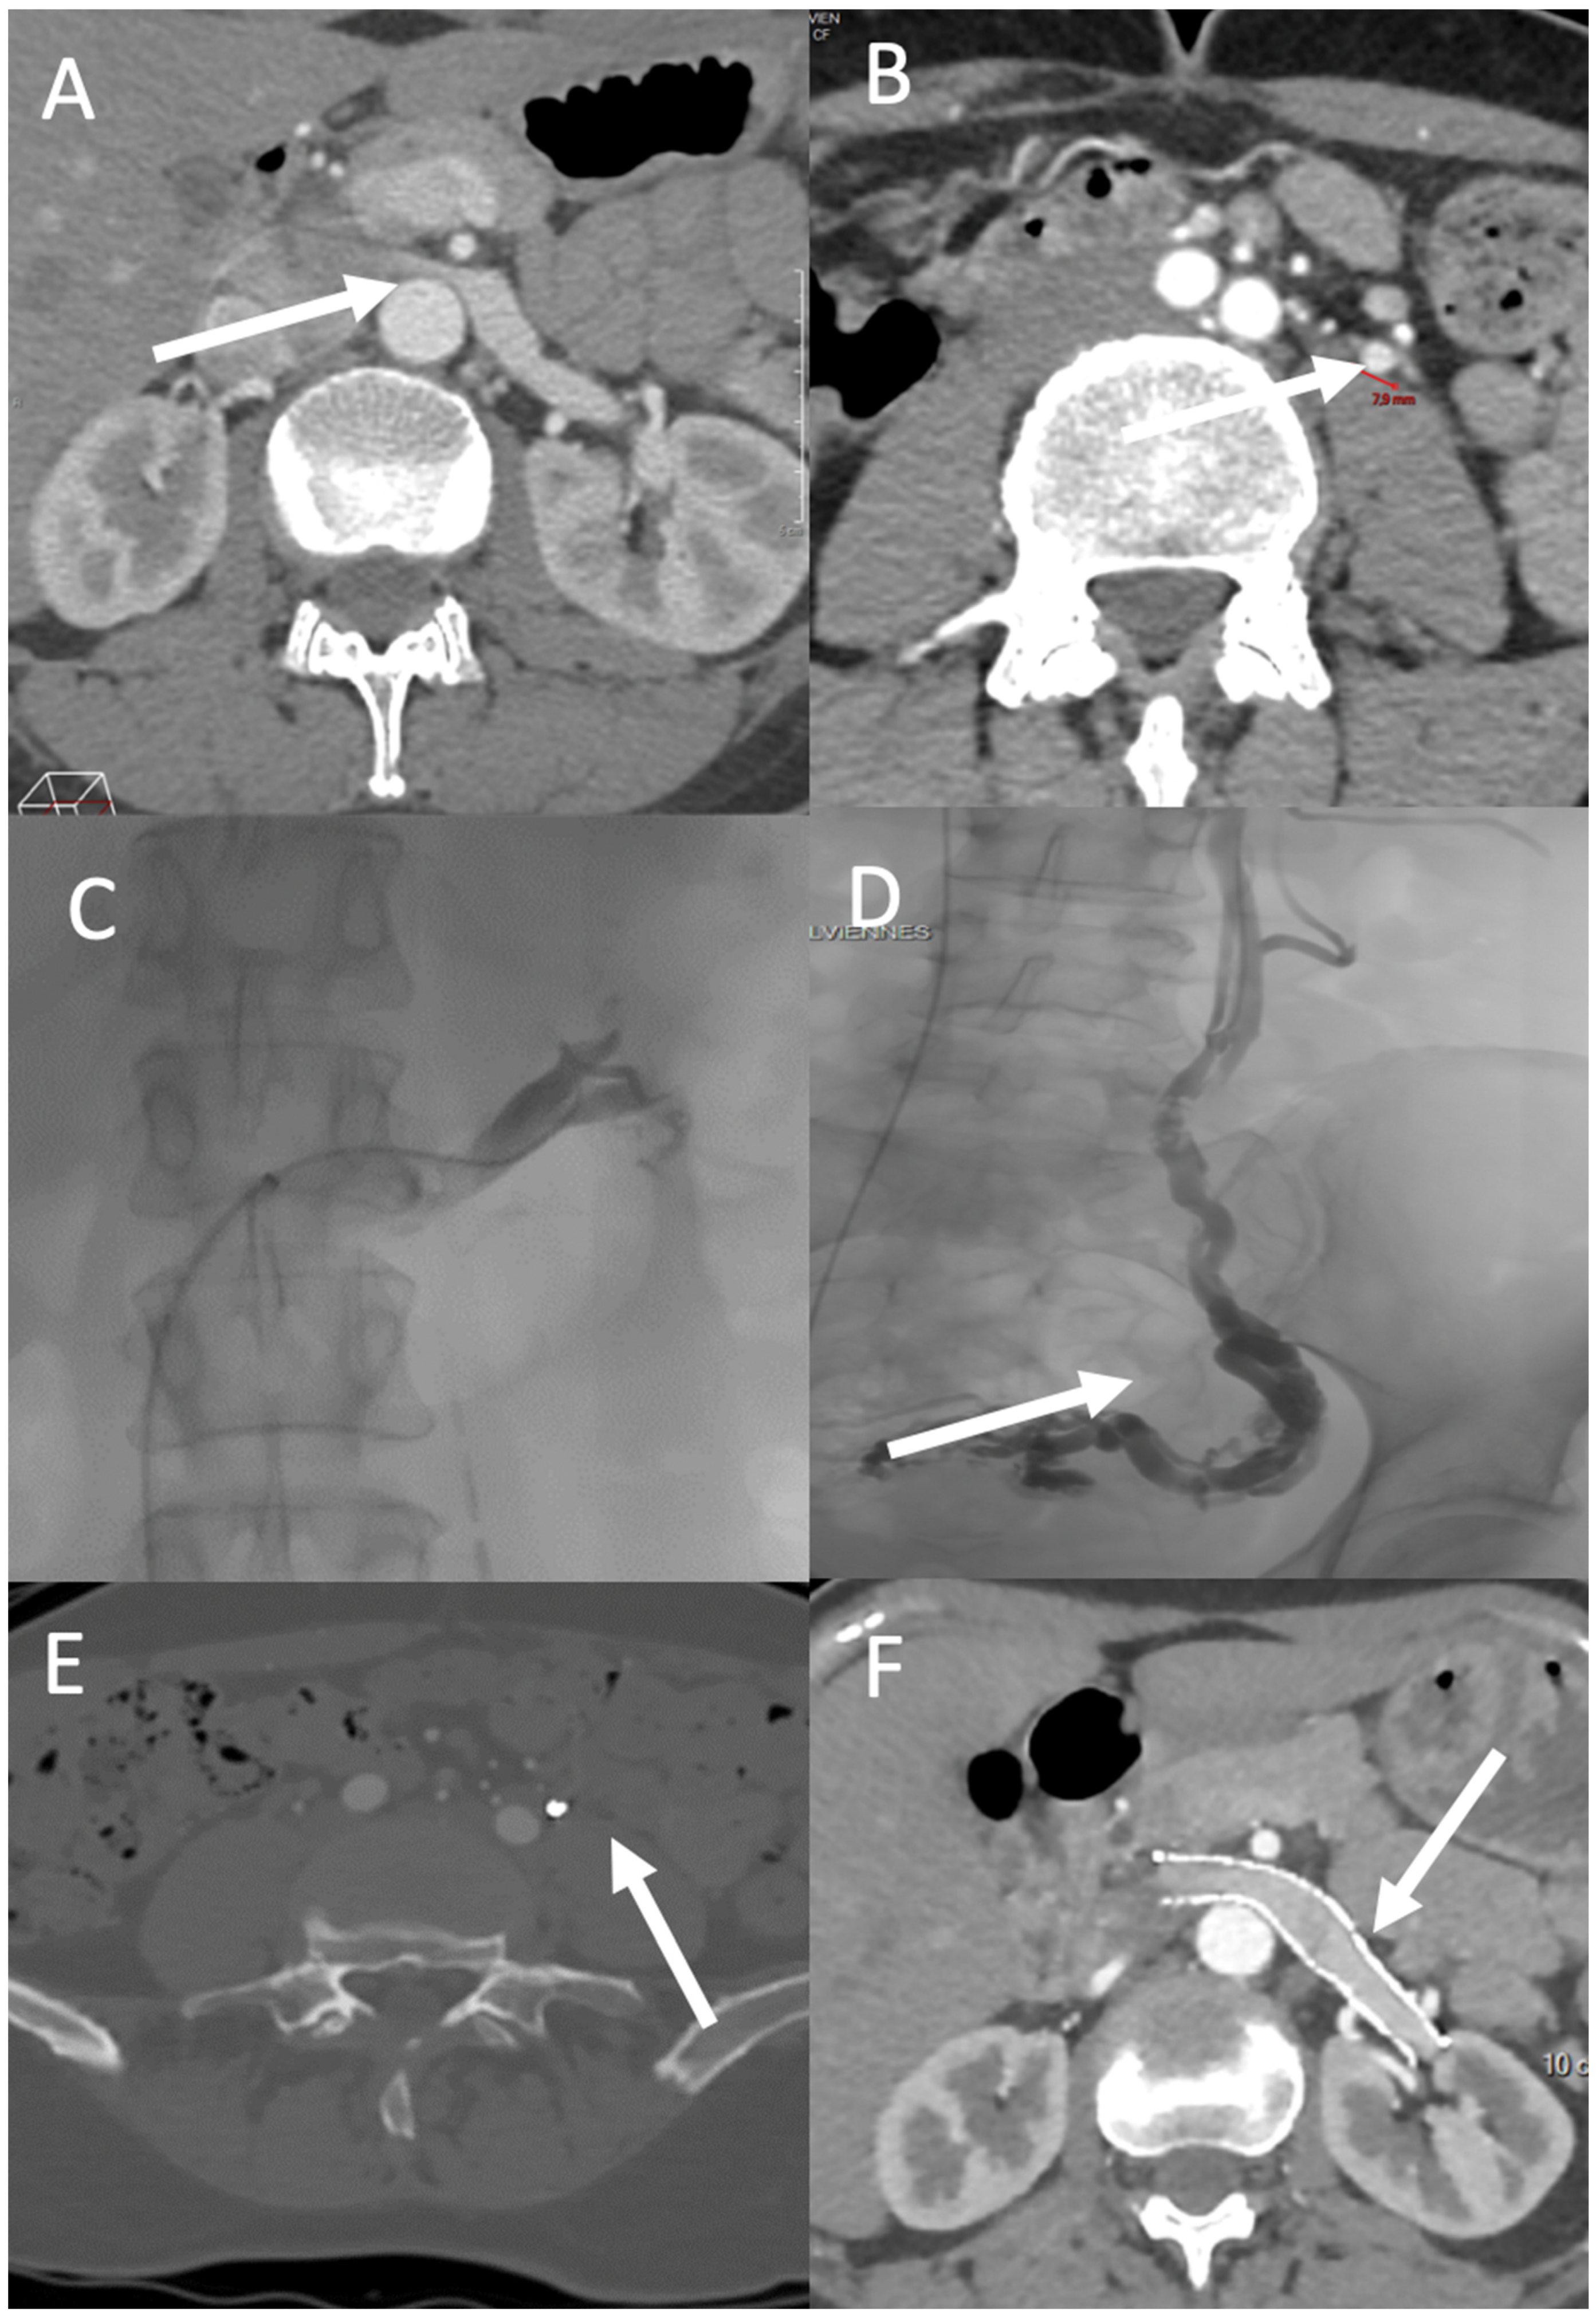

4.1. Nutcracker Syndrome and May–Thurner Syndrome

4.2. Ovarian and Iliac Venous Insufficiency

4.3. Vulvar and Lower Limb Varices of Pelvic Origin